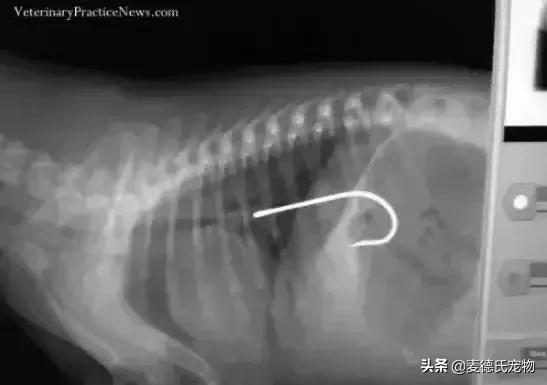

鱼钩...